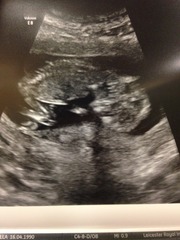

We had our scan at 8am this morning. In and out nice and quick. I got my bloods done at the same time. All good - phew! Baby was waving and wiggling its little stumps (?!) Measuring 11 weeks so EDD 11th Aug. I'm so relieved. I'm at work so I can't post the scan pic, but will do so later.

Elle so glad everything went well for you, post a pic when you can!

bear for the first day in weeks I am ketone free which is good. I've discovered I can seem to eat Mac cheese so trying to focus on that. I'm due back at work a week today so hoping this is it. We have our NHS scan tomorrow afternoon so can't wait for that.

Thats great news lily!! Brilliant you are able to manage mac and cheese and hopefully this is the start of you feeling much better and back to work next week. What time's your scan tomorrow? Will be thinking of you.

Four what a great scan. My little one really loves to hide so I can see me having to do all the moving about too